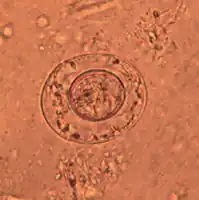

Tasemnice dětská je nejmenší lidskou tasemnicí, dospělec dorůstá nanejvýš do délky 40 mm. Jeho ploché bělavé tělo se skládá ze 100 až 200 článků. Každý z článků obsahuje samčí i samičí reprodukční orgány. Oplodněný článek dále vytváří vakovité útvary naplněné vajíčky, ta jsou velká asi 50 μm. Vajíčka jsou oválná, bezbarvá a jejich množství v jednom článku se pohybuje mezi 80 až 200 kusy. Na hlavičce se nachází 4 přísavky a krátký vysouvací chobotek s 20 až 30 háčky uspořádanými do kruhu, které napomáhají k uchycení v lumenu střeva.